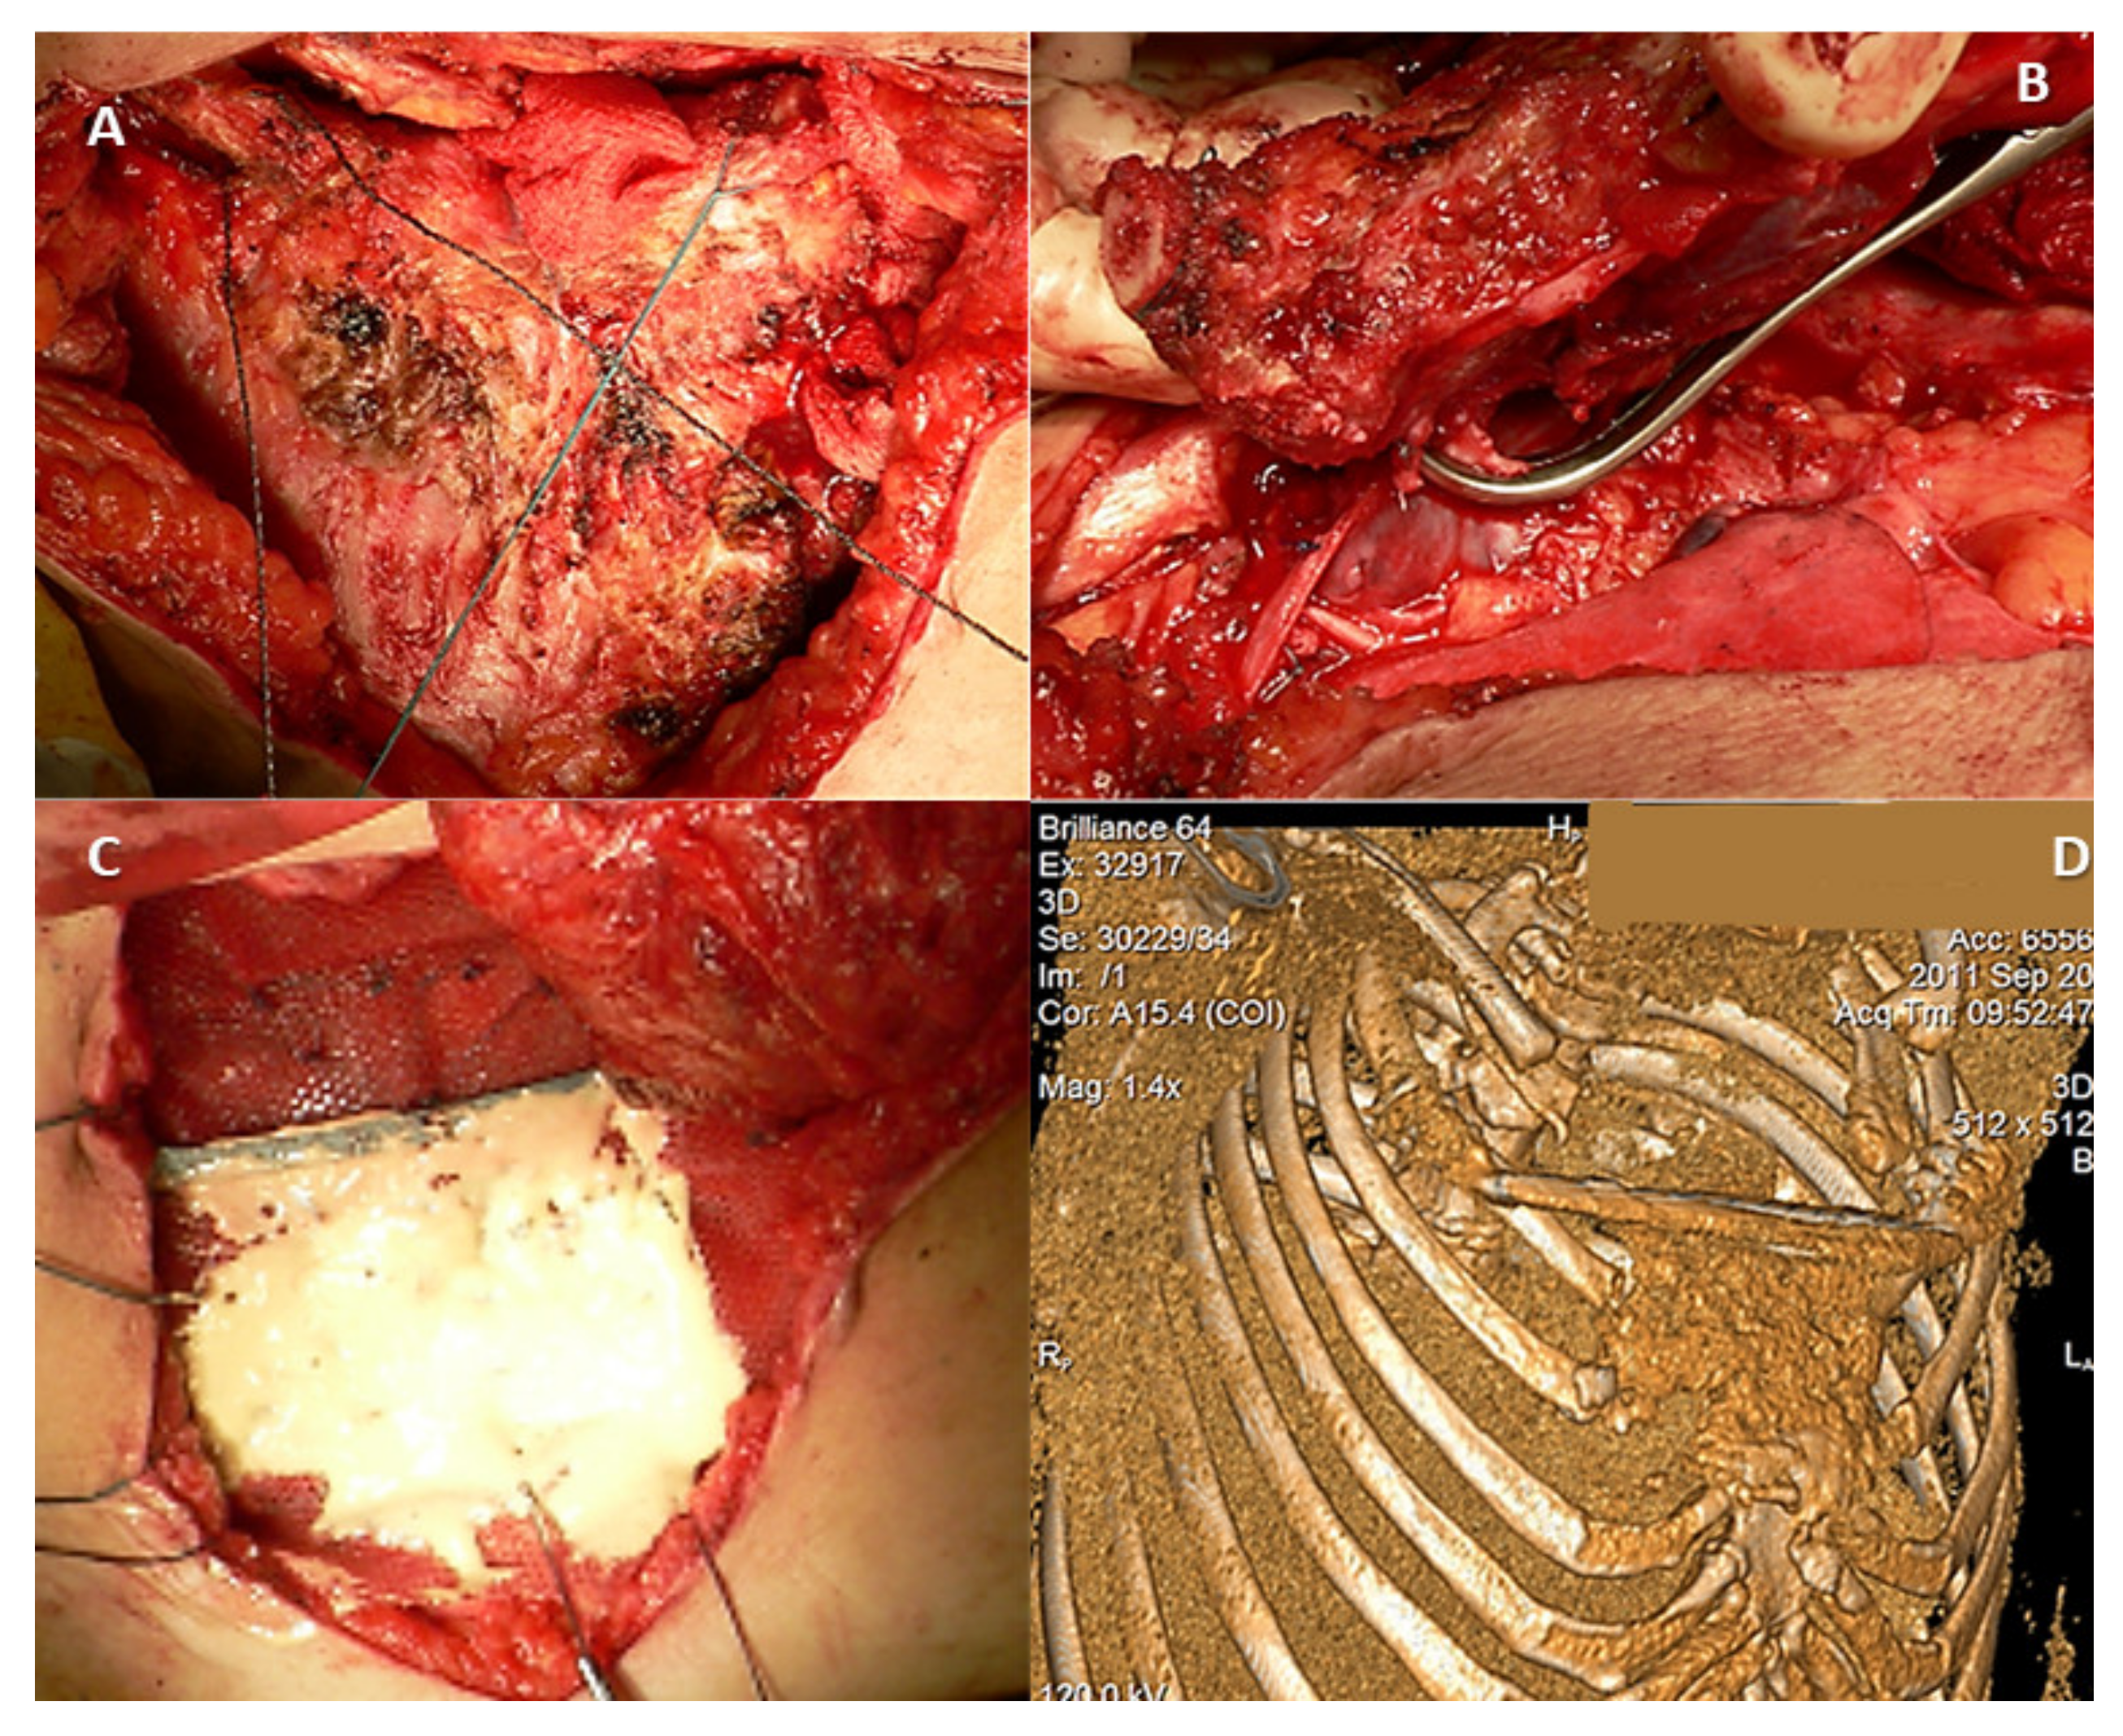

Figure 3.

Intraoperative aspect of a 64-year-old patient diagnosed with a manubrial tumor. A Gigli wire saw (A) was used for en bloc bilateral resection of the medial third of the clavicles, the cartilaginous portion of the first rib, and the manubrium (B). (C) Polypropylene mesh and Kryptonite cementum were used for rigid anterior chest wall reconstruction. (D) A 3D-CT scan reconstruction at three months after surgery shows the neo-sternum.

In the case of a primary chest wall tumor, a 4 to 5 cm tumor-free margin must be achieved, and the immediate adjacent ribs should also be resected [37,38]. For metastasis, the rule described by Leonardi requires a 2 cm parietectomy away from the tumor. Sternal manubrium tumors require resection of the internal third of the clavicles [39]. Reconstruction is not required following manubrial resection, en bloc or not, with either one or both clavicles [37,38]. In a case series of manubrial malignant tumors, reconstruction was successfully performed with autogenous rib grafts [40]. However, if the tumor affects at least 3 or 4 ribs, a paradoxical rib cage might occur, preventing complete re-expansion of the contralateral lung after surgery [37,38,41,42,43,44,45].